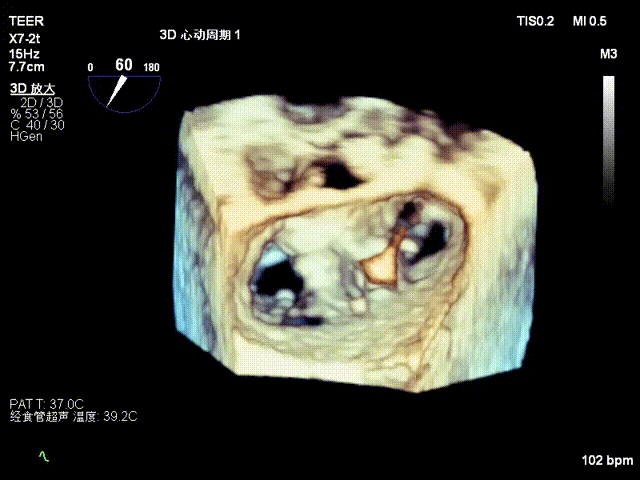

术前影像

左房极小

房间隔增厚

X-plane2区

X-plane2区彩色

3D

3D彩色